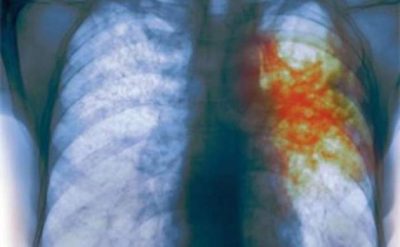

Министр здравоохранения Украины Максим Степанов заявил, что последствием так называемой оптимизации в сфере медицины, которая предусмотрена вторым этапом реформы, может стать вспышка туберкулеза в стране.

«Это не оптимизация, а банальное сокращение. Последствия будут такие, если мы сейчас не остановим этот процесс: как минимум, мы получим через 2-3 года рост заболеваемости на туберкулез на 30%. Увеличится и процент смертей из-за сокращения медработников, речь идет о тысячах медиков», – заявил Степанов.

Он подчеркнул, что не готов мириться с этим, и пообещал уже в ближайшие дни найти решение, как будут финансироваться противотуберкулезные диспансеры. Сейчас же, по словам министра, ситуация критическая – многим учреждениям не хватает до 80% необходимых денежных средств.